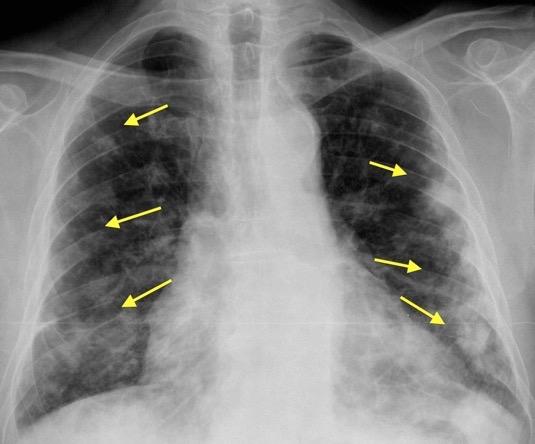

“ALAS DE MARIPOSA” . SIGNO DE . (butterfly shadow sign).(También. Bat´s wing)

Corazón normal

Edema no cardiogénico

Hemorragia/ IAM/CMV/ Drogas

Neumocistis

Electrolitos

Ahogamiento

Edema no cardiogénico. Ahogamiento. Se cayó borracho en una bañera de agua con lejía